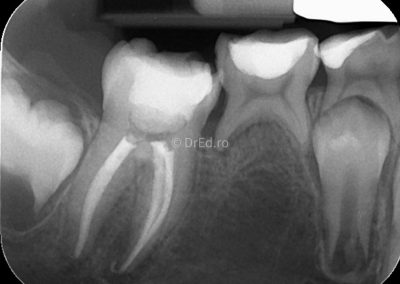

Galerie

Toate imaginile, fotografiile și radiografiile publicate pe acest site sunt protejate prin drepturi de autor și constituie proprietatea exclusivă a Dred.ro.

Aceste materiale sunt furnizate exclusiv în scop informativ și educațional și nu conțin date cu caracter personal sau informații care permit identificarea pacienților, în concordanță cu legislația privind protecția datelor cu caracter personal și GDPR.

Reproducerea, copierea, distribuirea, publicarea, transmiterea, modificarea sau orice altă utilizare, integrală ori parțială, a acestor materiale, în orice formă și prin orice mijloace, fără consimțământul prealabil scris al titularului drepturilor, este strict interzisă și poate atrage răspunderea civilă și/sau penală, în condițiile legii aplicabile privind drepturile de autor și protecția proprietății intelectuale.